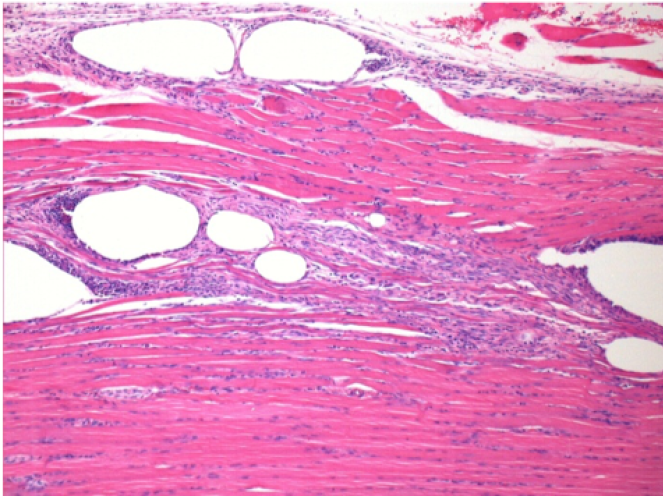

0.5 ml ( 5x 0.1ml) Endopeel SC Injection in the right subcutaneous pretibial area.

L:200x-Control-SC

R-D10-SC-200X